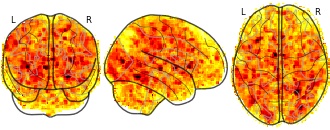

Citation: Hur, J., Kaplan, C. M., Smith, J. F., Bradford, D. E., Fox, A. S., Curtin, J. J., & Shackman, A. J. (in press). Acute alcohol administration dampens central extended amygdala reactivity. Scientific Reports.

Alcohol use is common, imposes a staggering burden on public health, and often resists treatment, underscoring the need to develop a deeper understanding of the underlying neurobiology. The central extended amygdala (EAc)—including the bed nucleus of the stria terminalis (BST) and the central nucleus of the amygdala (Ce)—plays a key role in prominent neuroscientific models of alcohol drinking, but the relevance of these regions to acute alcohol consumption in humans remains unknown. Using a single-blind, randomized-groups design, multiband fMRI data were acquired from 49 social drinkers while they performed a well-established emotional faces paradigm after consuming alcohol or placebo. Relative to placebo, alcohol significantly dampened reactivity to emotional faces in the BST. To rigorously assess potential regional differences in activation, data were extracted from unbiased, anatomically predefined regions-of-interest. Analyses revealed similar levels of dampening in the BST and Ce. In short, alcohol transiently reduces reactivity to emotional faces and it does so similarly across the two major divisions of the human EAc. These observations reinforce the translational relevance of addiction models derived from preclinical work in rodents and provide insights into the neural systems most relevant to the consumption of alcohol and the initial development of alcohol abuse in humans.Subject species

homo sapiens

Modality

fMRI-BOLD

Analysis level

group

Cognitive paradigm (task)

emotion processing fMRI task paradigm

Map type

T

- a